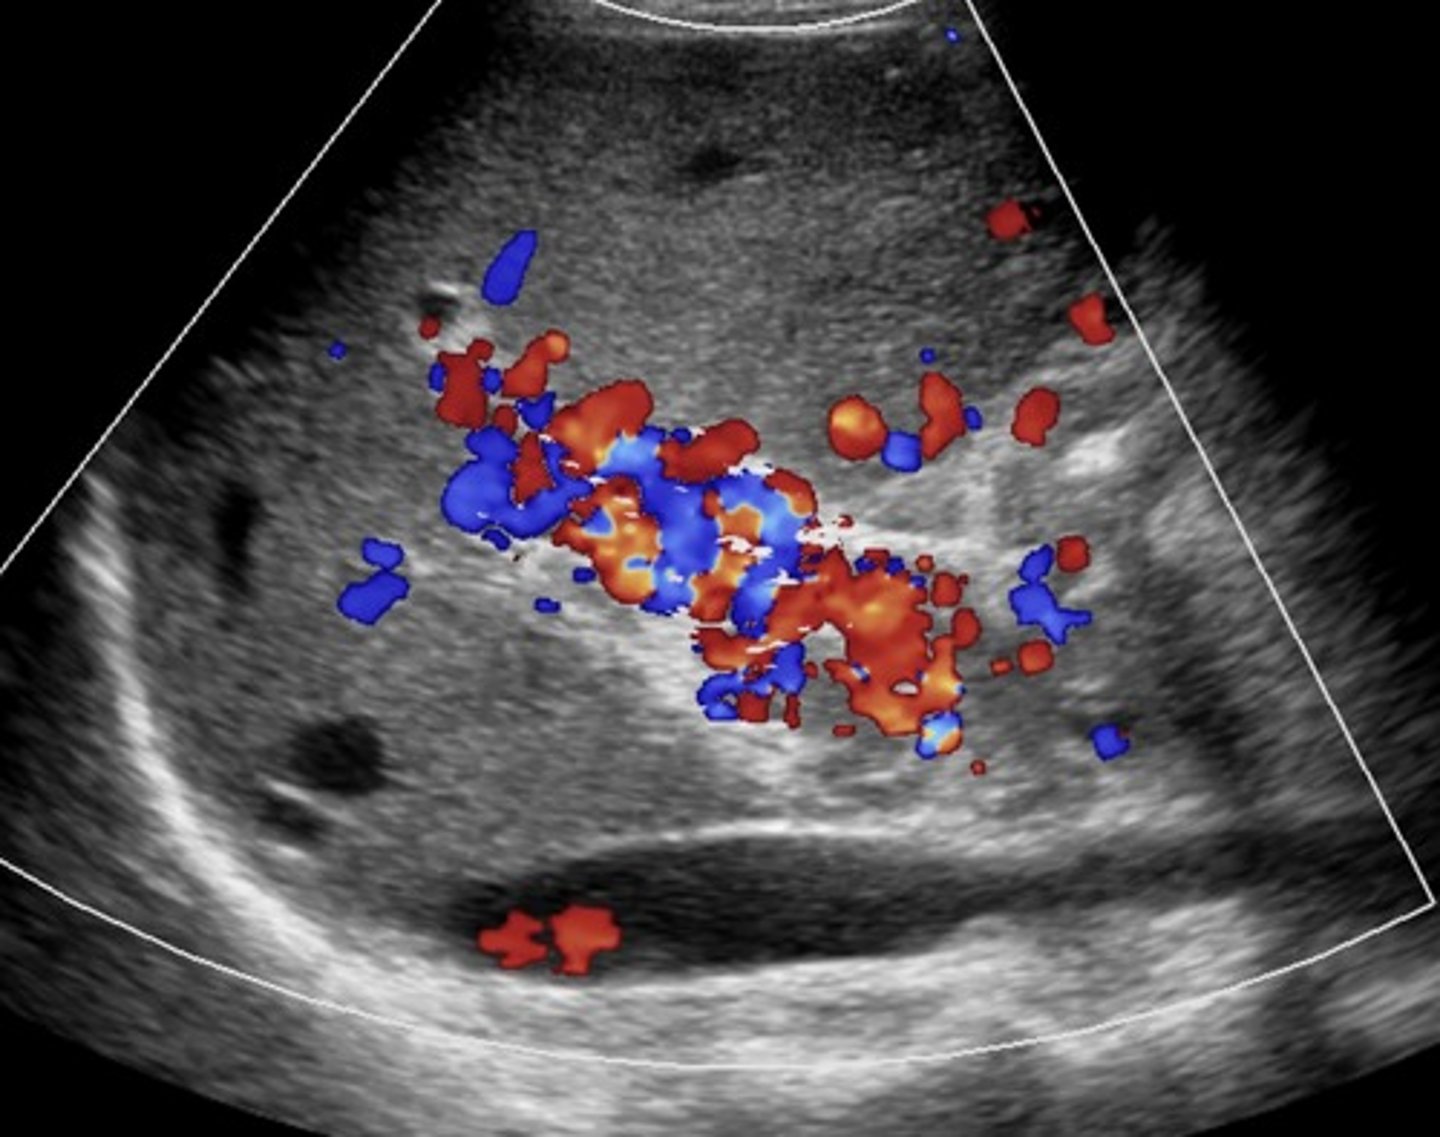

Cavernous Transformation

Due to chronic portal vein thrombosis

Occurs within 6 days after thrombotic event

Absent portal vein flow

Formation of new peri-portal vessels around portal vein

Hepatopetal flow within serpentine vessels